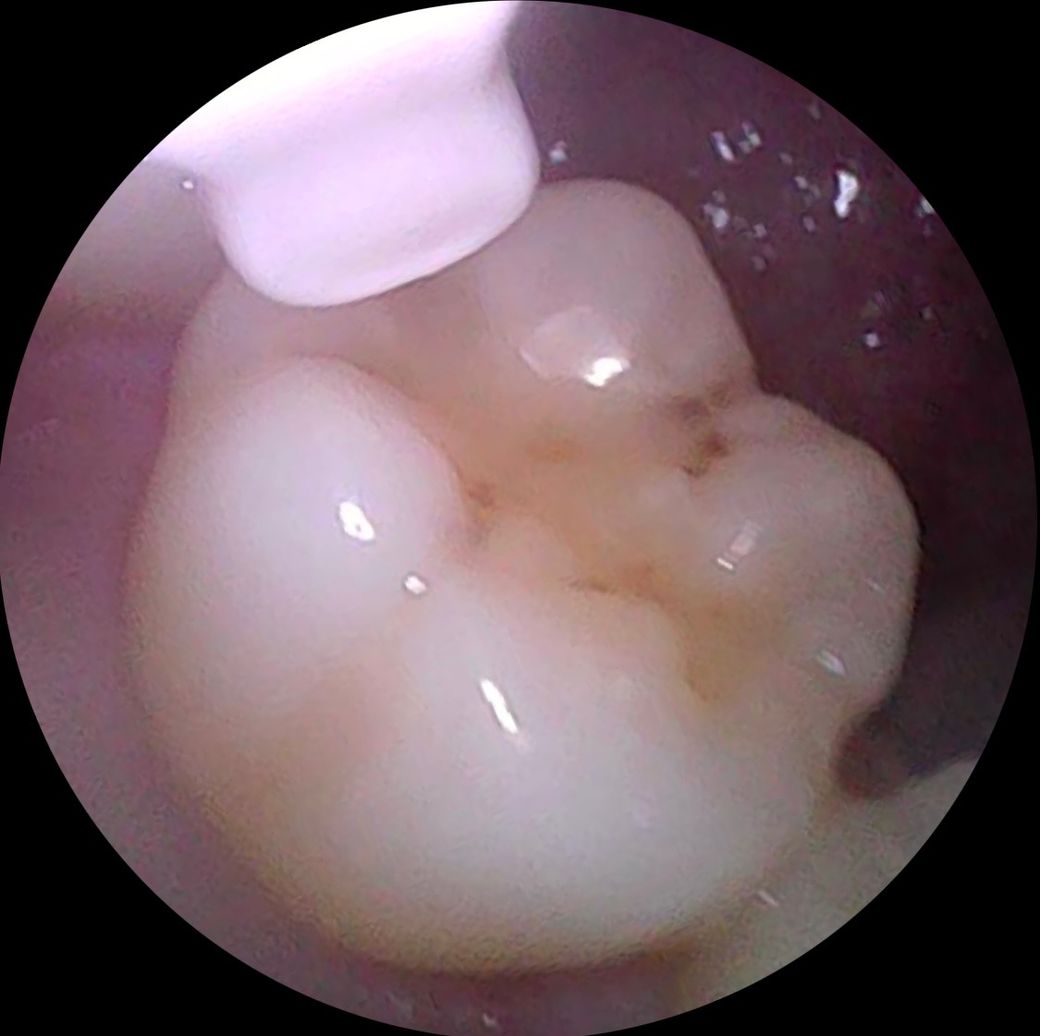

• 2번 째 사진

엑스레이를 찍어봐야 정확히 알겟지만,첫번째 치아는 충치가 상당히 진행된거 같고 나머지 치아의 충치는 간단한 충치 같습니다.

2,3,4,6번째는 충치가 그렇게 크진 않습니다 치료가 필요한 정도일지는 엑스레이 찍어봐야합니다